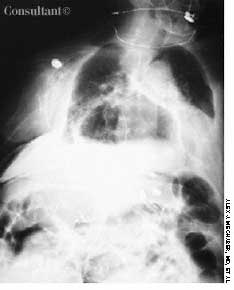

With a 1-year history of episodic wheezing, a 62-year-old woman (a smoker for the past 30 years) was being treated for bronchial asthma, but bronchodilator therapy did not control her symptoms. She was hospitalized with worsening dyspnea and a 4.5-kg (10-lb) weight loss over the past 3 months. There was no hemoptysis.